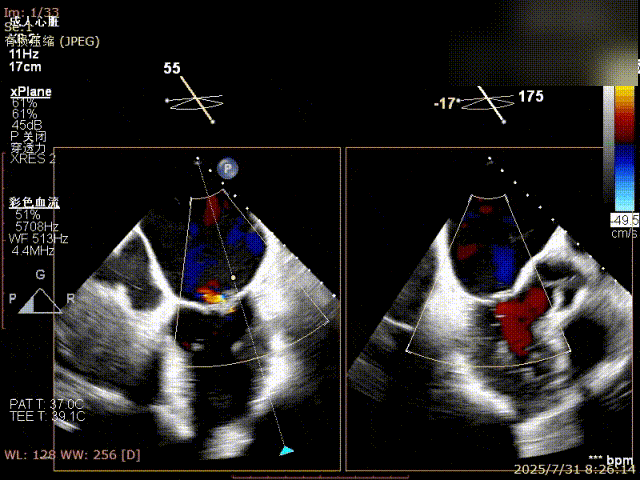

术前完善经食管超声评估,提示该患者双房大,二尖瓣重度反流4+伴后叶脱垂、后叶部分腱索断裂。根据评估结果,心脏大血管外科王安彪主任团队制定了周密的手术方案:植入一枚夹合器,钳夹P1区反流最大处,尽可能夹持全部后叶脱垂瓣叶组织,后续根据术中实时残余分流和跨瓣压差等指标,并依据实时超声监测调整治疗策略。

三维评估

二尖瓣P1脱垂偏心性返流

术前影像